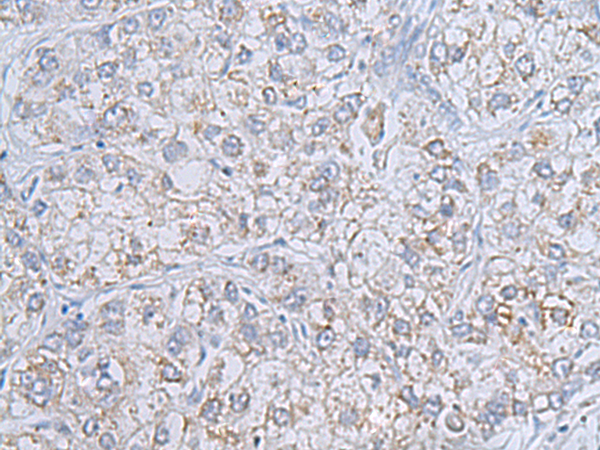

分类: 科研抗体货号: P01696别名:应用: WB,IHC反应种属: Human, Mouse